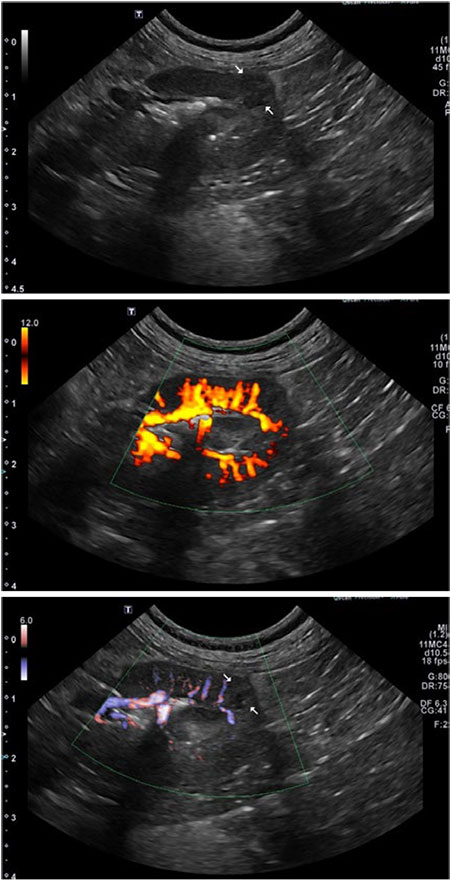

시술 후 환자는 특이사항 없이 잘 지냈다. 수술 후 4일째 초음파 recheck을 하였다. 좌측 신장 수질부 낭성 저에코성 구조물이 관찰되며, 신장피막부로 돌출되어 관찰되었다. 좌측 신장의 낭성 구조물내 출혈 소견이 의심되고, 주변 지방의 에코 상승 소견이 관찰되었다.

술 후 28일 째 초음파 recheck을 하였다. 좌측 신장 caudal pole에 존재하던 cystic lesions은 더 이상 확인되지 않으며, 해당 부위는 비균질한 저에코와 불규칙한 변연을 보이는 focal lesion으로 확인되었다.

해당 병소로 인해 신장 변연은 경도로 irregular하게 확인되었다. 해당 병소에서 Color Doppler 적용 시 vascular flow는 확인되지 않았다. 시술을 한 좌측 신장엔 이전에 있는 cyst는 없어지고, 작은 scar tissue 혹은 granuloma로 의심되는 병소만 남았다.